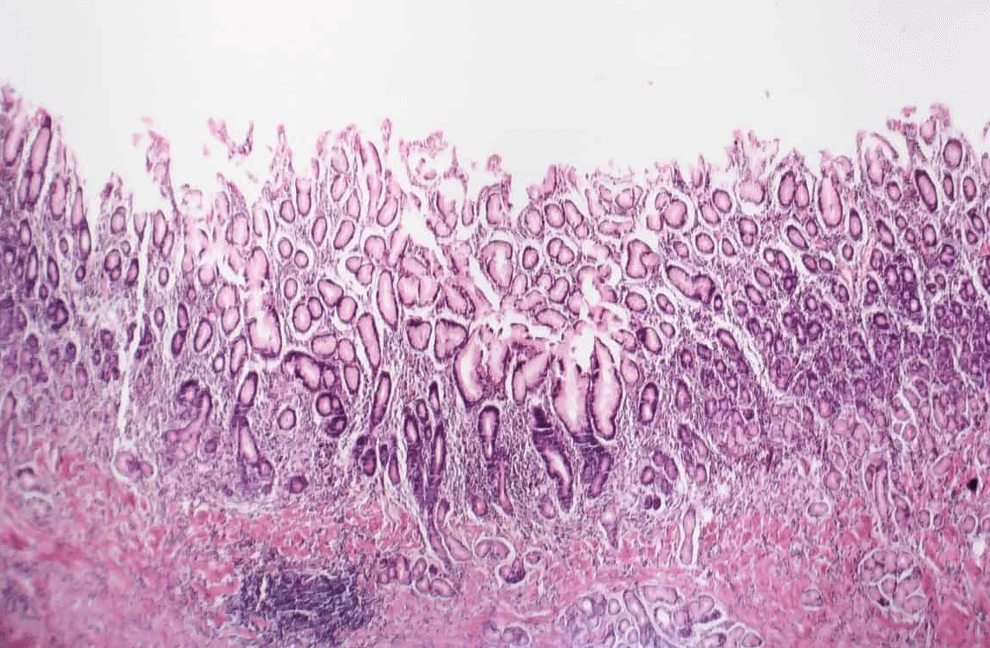

미란성 위염은 위 점막에 염증으로 인하여 손상이 지속적으로 반복되는 상태를 이야기하며, 위내시경 검사를 통해 확인할 수 있습니다. 미란성 위염을 방치하거나 치료시기를 놓칠 경우 증상이 악화되어 위궤양 또는 출혈로 진행될 수 있으니 아래와 같은 증상이 나타나면 병원에 가보시는 것도 중요합니다.

미란성 및 출혈성 위염의 위 병증의 내시경 소견은 점상 출혈에서 미란 및 궤양에 이르기까지 다양합니다. 출혈성 병변은 원인 인자에 따라 강도와 분포가 다를 수 있습니다. 침식 성 변화는 일반적으로 궤양 형성으로 진행될 수 있는 여러 침식에 의해 나타납니다.